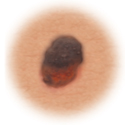

Asymmetry

When half of the mole does not match the other half

Border

When the borders (edges) of the mole are ragged or irregular

Color

When the color of the mole varies throughout

Diameter

If the mole's diameter is larger than a pencil's eraser